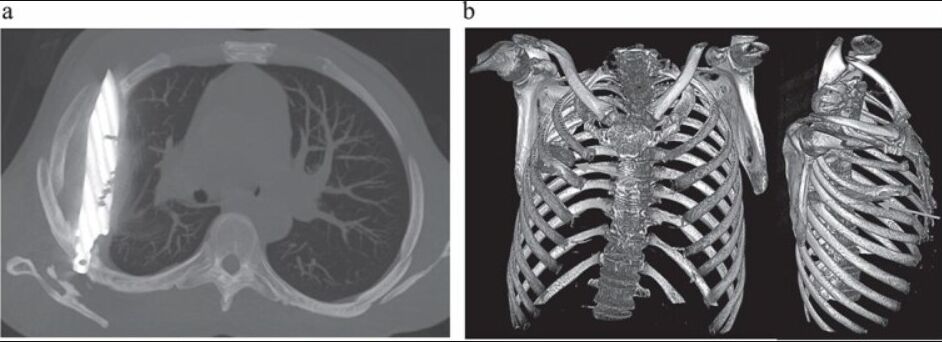

未料,X光檢測結果令醫師大感震驚,因為畫面清楚顯示,患者胸腔內有一個利刃狀的「金屬殘留物體」,從肩胛骨穿入,周圍被膿液和壞死組織包圍。

醫師詢問之後,患者回憶起8年前「捲入一場激烈衝突」,當時臉部、背部、胸部和腹部均遭到多處刀傷。由於當地醫療資源有限,他僅接受表面傷口縫合等基本急救處理,未進行其他進一步檢查,接下來的8年裡毫無異常。

在醫師安排下,患者立即接受手術取出刀片,術後恢復良好,10天後順利出院。

醫療團隊表示,雖然「患者身體成功將異物包覆在纖維囊內,限制了發炎和組織損傷」,但乳頭流膿代表即將開始出現嚴重併發症。他們警告,這把殘留的刀子原本可能造成致命後果,呼籲改善資源匱乏地區的創傷處理規範與醫療設備配置。